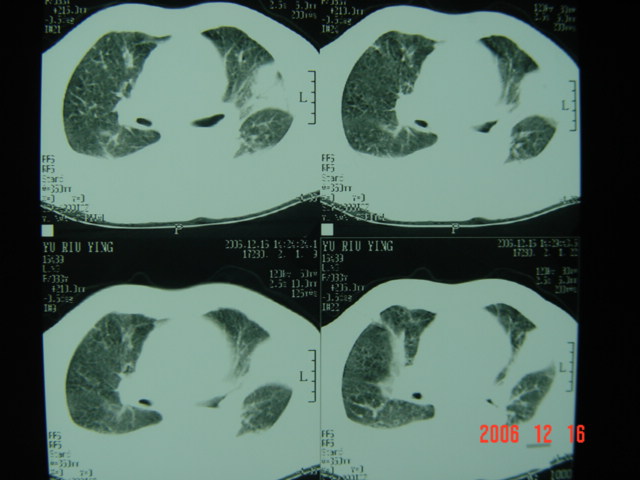

标题: CT5663:女、83岁,轻微咳嗽、左下胸痛。 [打印本页]

标题: CT5663:女、83岁,轻微咳嗽、左下胸痛。

左第八肋腋侧呈膨胀性骨质破坏,内侧见软组织密度肿块。左肺舌段呈楔形实变,基底近胸壁,尖端向肺门。双侧胸壁后缘见新月形水样密度区。

考虑:1、左第8肋骨转移瘤;

2、左肺舌叶肺栓塞可能性大;

3、双侧中量胸腔积液。